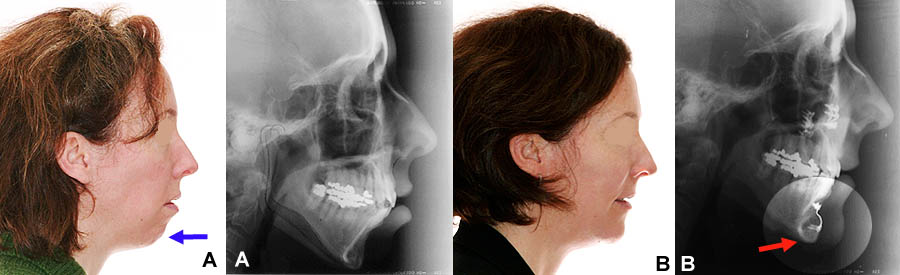

(A) Femme de 45 ans avec un menton reculé. La mâchoire supérieure a été “remontée” (impaction maxillaire) et le menton a été avancé (génioplastie) pour donner plus de volume et améliorer le profil. (B) La plaque et les vis chirurgicales de rétention du menton (flèche), ainsi que les vis à la mâchoire supérieure, sont visibles sur la radiographie post-opératoire.